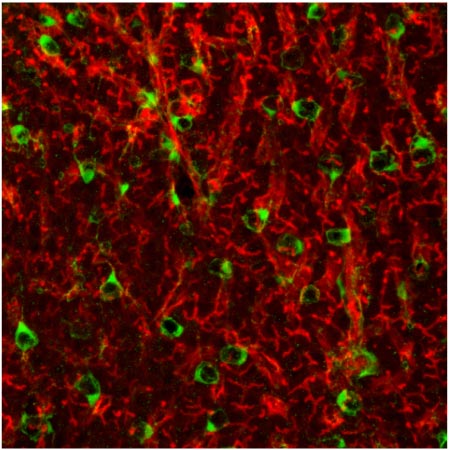

We developed the first zebrafish reporter line of hepatic stellate cells and showed that the zebrafish hepatic stellate cells share many similarities with their mammalian counterparts, including morphology, location, lipid storage, gene expression profile, and responses to liver injury.

Currently, we are using the power of imaging and genetics in zebrafish to investigate the contribution of hepatic stellate cells to liver development and regeneration. We also study the molecular mechanisms underlying their activation in liver injures induced by alcohol and other hepatic toxins. Finally, we are conducting high throughput chemical screens to identify drugs that influence the development and activation of hepatic stellate cells.